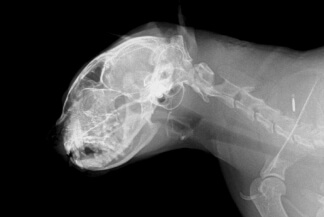

Рентген головы кошкам

Рентген головы кошки или кота является одним из эффективных методов диагностики. Он основан на способности тканей по-разному пропускать рентгеновские лучи и фиксировать полученный результат на экране компьютера, пленке или специальной бумаге. С помощью данного метода диагностики можно определить состояние костей черепа, лицевого скелета, головного мозга. На основании рентгеновского исследования головы животного ветеринар ставит диагноз и назначает соответствующее лечение.

Рентгенографию головы кошки назначает только ветеринарный врач. Она помогает выявить следующую патологию:

• Травму головы в результате падения с высоты, защемления дверью, окном, транспортной аварии, драке с другими животными и т.п.).

• Врожденную или приобретенную асимметрию морды или костей черепа.

• Онкологические процессы (доброкачественные, злокачественные опухоли).

• Болезни придаточных пазух носа (околоносовых синусов).

• Резкое падение слуха или зрения, или и того и другого.

Как проводится исследование головы?

Процедура проводится в присутствии хозяина питомца. Кошку укладывают на специальный стол, придерживая ее руками так, чтобы зафиксировать голову в нужном положении на несколько секунд.

Снимки выполняют в нескольких проекциях, чтобы рассмотреть патологию как можно объемнее и без наложения теней от других участков на исследуемую область.

В некоторых случаях животному делают седацию, чтобы успокоить его и провести диагностическую процедуру максимально эффективно.